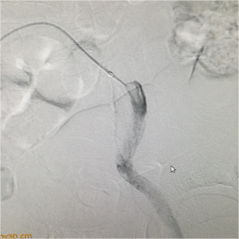

手术当天,易主任在病人左下肢动脉多处进行造影,考虑为血栓造成动脉闭塞,导管退至左侧髂外动脉起始部行溶栓治疗。